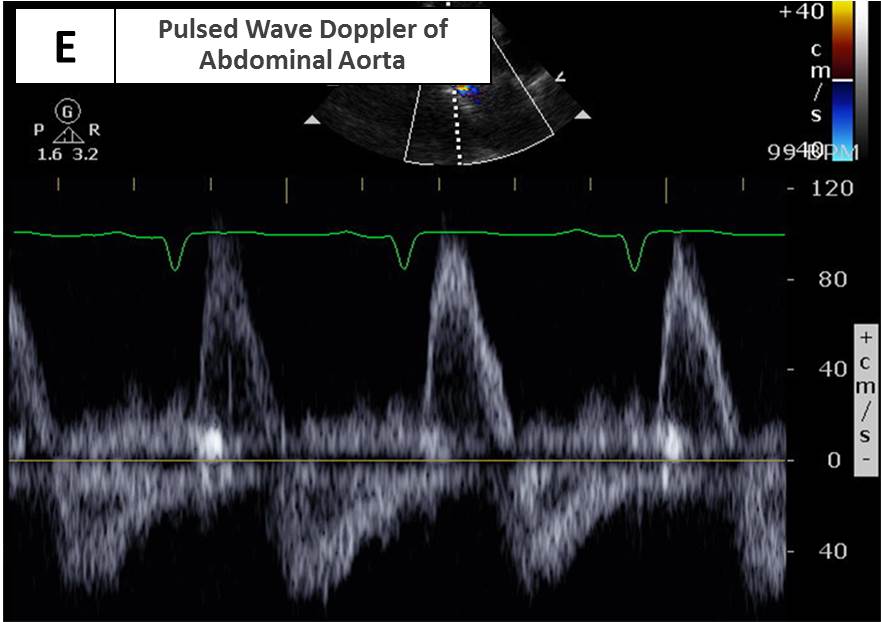

Explanation for Answer E

Normally there is only brief retrograde flow in the descending thoracic and abdominal aorta that occurs in early diastole. With severe AR, whether acute or chronic, the retrograde flow in the descending thoracic and abdominal aorta occurs throughout diastole. Holodiastolic flow reversal in the abdominal aorta, as shown in Figures 5 and 10, is a more specific sign of severe AR than holodiastolic reversal in the descending thoracic aorta.

Figure 10